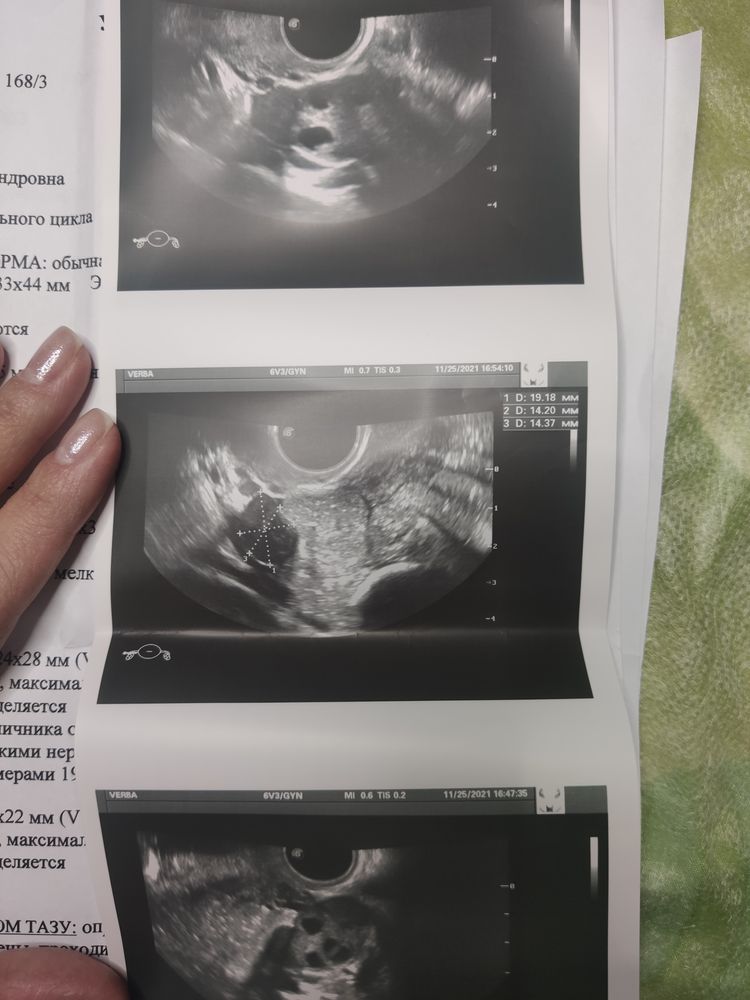

УЗИ малого таза

Сходила планово провериться на УЗИ органов малого таза. Я как чувствовала. Никогда никаких проблем не было и вот врач находит какое-то образование на яичнике. Понять что за оно,она не смогла. Направила сдать онкомаркер (он в норме). В понедельник на МРТ. Может кто-то сталкивался с похожим?

Cмущает тут именно кровоток (васкулярное при ЦДК), только не совсем понятно- в центре она разглядела или по капсуле. Однако остальные описания присущи кисте. Да и степень риска у Вас 3 (о- rads 3), по этой классификации вероятность чего-то злокачественного очень низка.